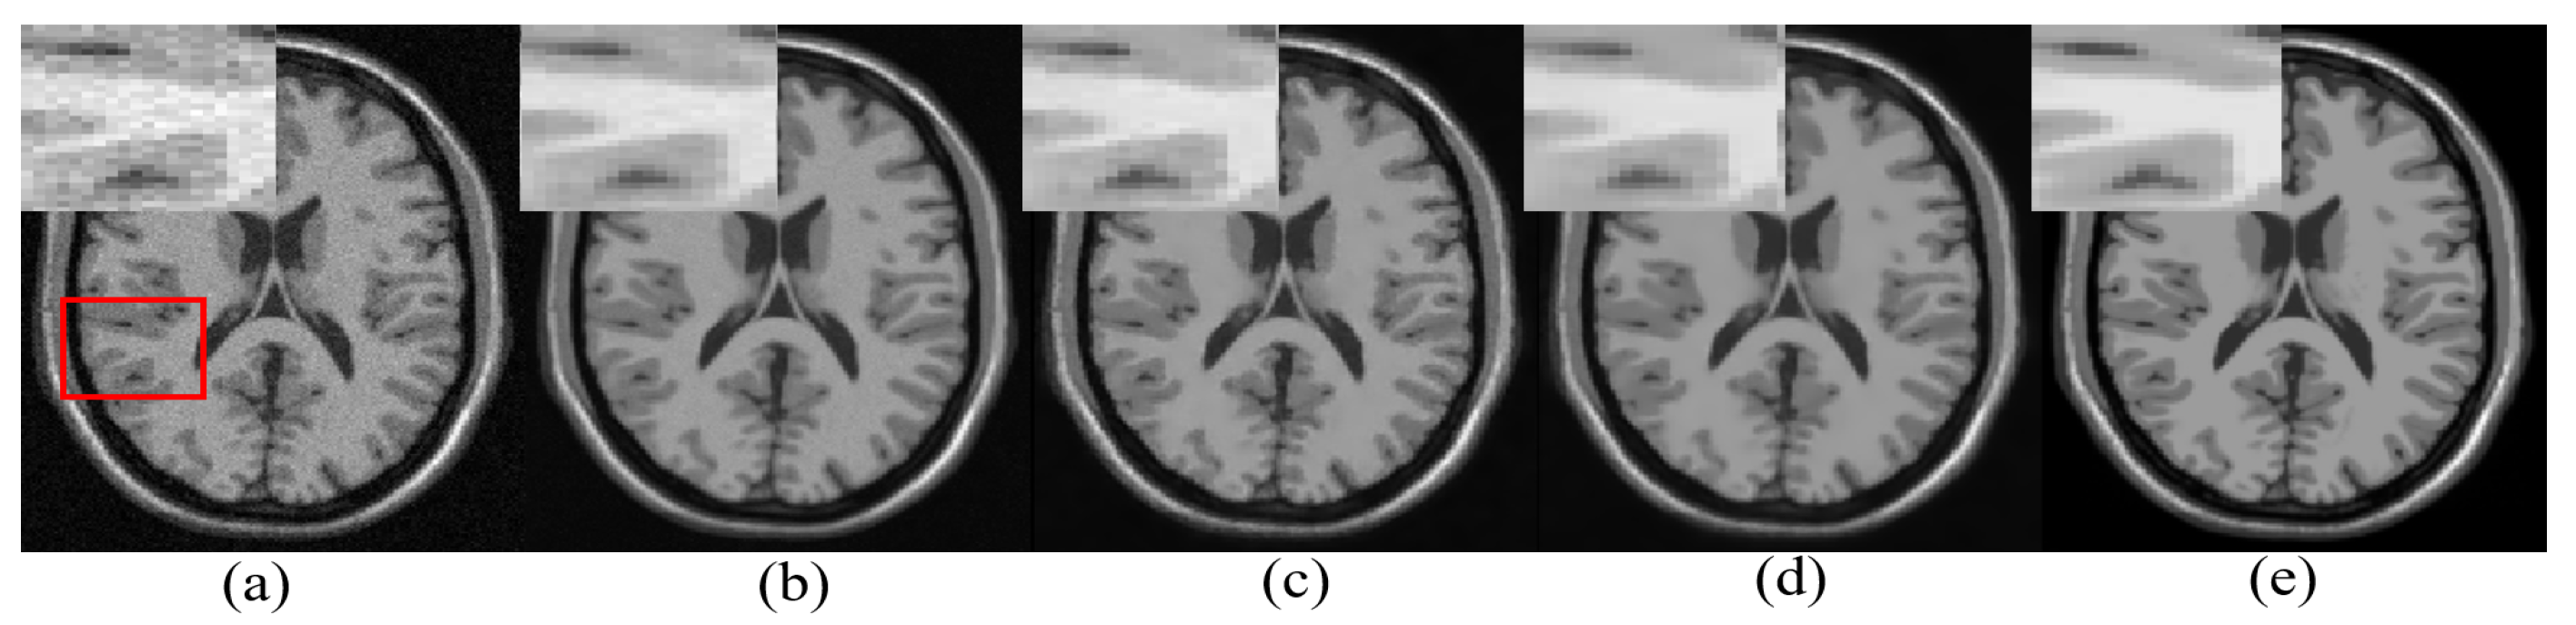

One real MR image is randomly selected, degraded with 2% Gaussian noise, and is denoised using different algorithms. The denoised images are shown in Figure 6. It can be observed that the proposed approach has reduced smearing of image details (in the yellow box), provides efficient denoising in the smooth region, and estimates edges with comparable quality to existing methods in the cyan box in Figure 6.

Figure 6.

Demonstration of image denoising achieved by different denoising algorithms on real MR images with synthetically added 2% Gaussian noise. From left to right—noisy image, optimized blockwise non local means (ONLM) [57], multi-resolution based ONLM (MRONLM) [41], oracle based discrete cosine transform (ODCT), PCA-based denoising over ODCT (PRINLM) [35], variance stabilized transform with blockwise matching and 4D filtering (VST-BM4D) [25], adaptive ONLM (AONLM) [40], the proposed approach, and the original noiseless image.